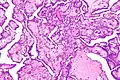

Histological features of normal cells and cancer cells

Cancer cells have distinguishing histological features visible under the microscope.[12][13] The nucleus is often large and irregular, and the cytoplasm may also display abnormalities.[14]

Nucleus

The shape, size, protein composition, and texture of the nucleus are often altered in malignant cells. The nucleus may acquire grooves, folds or indentations, chromatin may aggregate or disperse, and the nucleolus can become enlarged. In normal cells, the nucleus is often round or solid in shape, but in cancer cells the outline is often irregular. Different combinations of abnormalities are characteristic of different cancer types, to the extent that nuclear appearance can be used as a marker in cancer diagnostics and staging.[15]